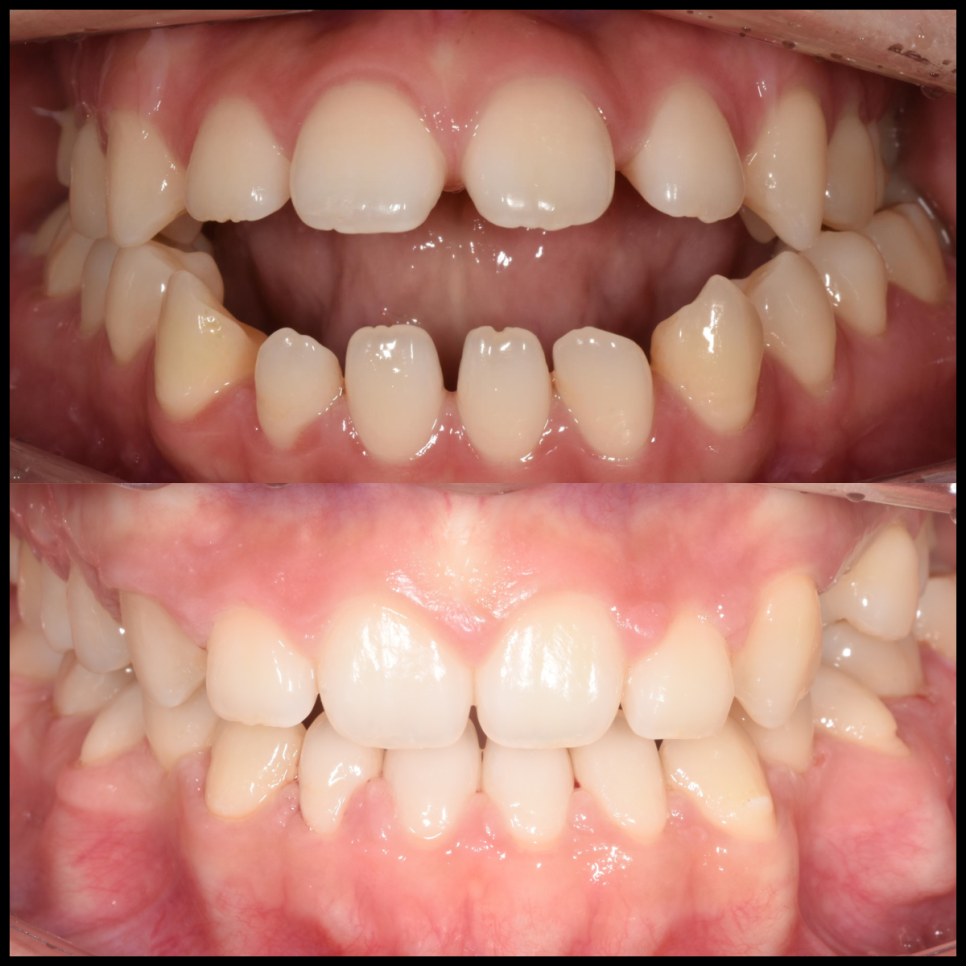

치료 결과

이렇게 모든 치료가 끝났습니다. 환자분의 처음 고민이었던 세 가지 문제가 어떻게 개선 되었는지 다시 한 번 정리해보겠습니다.

앞니 개방교합의 해소

좁았던 입천장이 넓어지자 갈 곳 없던 혀가 자연스럽게 제자리를 찾게 되었습니다. 혀가 앞니를 밀어내던 힘이 사라지면서, 붕 떠 있던 앞니들이 비로소 정상적으로 맞물리기 시작했습니다. 이제는 음식물을 앞니로 편하게 끊어 드실 수 있게 되었고, 미소도 훨씬 예뻐졌습니다.

돌출입 증상의 개선

치아들이 배열될 충분한 공간이 확보되자, 앞으로 뻗어 있던 치아들이 제 위치로 들어갔습니다. 이 과정에서 입술 라인이 자연스럽게 뒤로 이동하며, 환자분이 원하셨던 세련되고 편안한 입매가 완성되었습니다.

안면 비대칭의 완화

양쪽 어금니의 교합 높이를 균일하게 맞추는 정밀한 조정 과정을 거쳤습니다. 특히 미니 스크류를 이용해 윗니를 살짝 압입시켜 우측 턱이 더 깊게 물리도록 유도한 결과, 골격적 한계가 있었음에도 불구하고 육안으로 보이는 얼굴 비대칭이 개선되었습니다.

수술 없는 교정, 진심을 담은 변화

모든 수술교정 케이스가 교정만으로 해결되는 것은 아닙니다. 골격적인 문제가 심한 경우에는 수술이 반드시 필요한 경우도 있습니다. 하지만 이번 환자분처럼 문제의 근본 원인을 정확히 파악하고 적절한 장치를 활용한다면, 수술 없이 충분히 만족스러운 결과를 얻을 수 있는 경우도 많습니다.